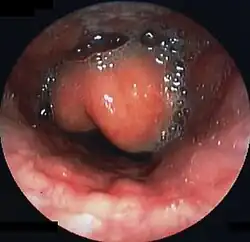

Swollen epiglottis in laryngoscopy

Diagnosis may be confirmed by direct inspection using a laryngoscope, although this may provoke airway spasm.[15] If epiglottitis is suspected, diagnosis is made on basis of fiberoptic laryngoscopy exam carried out in controlled environment like an operating room.[16][17]

On lateral C-spine X-ray, the thumbprint sign describes a swollen, enlarged epiglottis.[11] A normal X-ray, however does not exclude the diagnosis.[11] An ultrasound may be helpful if specific changes are present, but its use as of 2018 is in the early stages of study.[11]